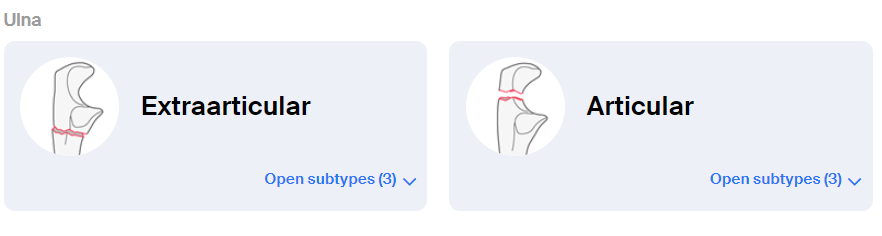

주두 골절의 분류

골절의 양상에 따라 치료 방법이 다르고, 치료의 결과가 달라지기 때문에, 골절을 정확하게 분류하는 것이 좋습니다. 척골 주두 골절을 분류하는 방법에는 몇가지가 있는데, 대표적인 것으로는

3. AO classification

세가지 분류를 많이 사용합니다.

3. AO

관절 외, 관절 내, 요골 머리 골절과 동반여부에 따라 분류합니다.